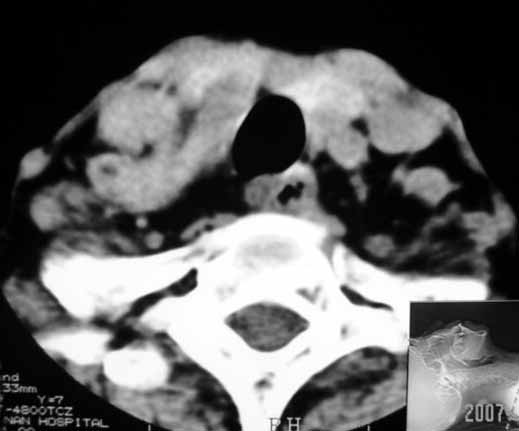

以下是引用jw-830在2007-5-24 15:33:00的发言:[br]右侧甲状腺增大,内可见低密度,病灶与周围软组织界线欠清晰,建议增强扫描除外甲状腺癌

以下是引用adams在2007-5-24 17:15:00的发言:[br]支持“ 右侧甲状腺增大,内可见低密度,病灶与周围软组织界线欠清晰,建议增强扫描除外甲状腺癌”。 [br] [br] [br][br] [br] [br]

以下是引用苯小孩在2007-5-24 15:26:00的发言:[br]左侧甲状腺腺癌或瘤,建议穿刺或核素进一步检查.